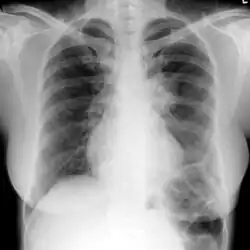

| Chest X-ray: widespread rounded lung nodules throughout both lungs | |

The extent of infection may be seen on X-ray or CT scan. On chest X-ray and CT, pulmonary aspergillosis classically manifests as a halo sign, and later, an air crescent sign.[21]